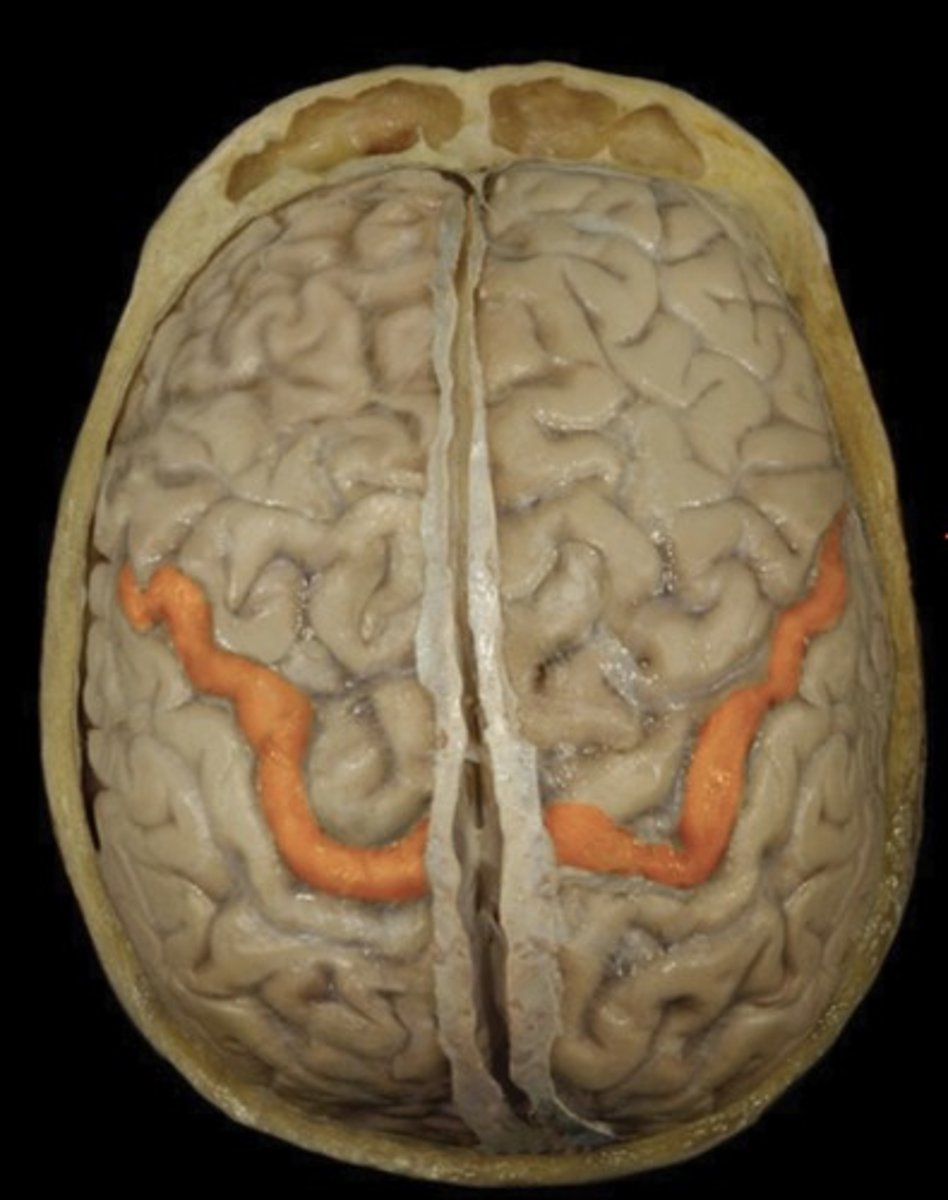

Central Sulcus

Name this structure

Precentral Gyrus (superior view)

Name this structure

Postcentral Gyrus (superior view)

Name this structure

Frontal Lobe (superior view)

Name this structure

Occipital Lobe (superior view)

Name this structure